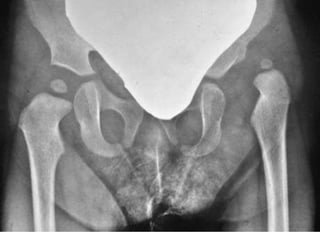

Direkt Radyografi Bulguları

• Epifiz çekirdeklerinin gözükmediği

dönemdeki bulgular erken radyografik

bulgulardır.

• Epifiz çekirdekleri ilk 5-6 ay ossifiye

olmadıkları için gözükmezler.

• Epifiz çekirdekleri gözükmeye başladığı

dönemdeki bulgular geç radyografik

• Direkt radyografilerde asetabulum dış

tarafında anormal sklerozun görülmesi

önemli bir bulgudur. Bu değişikliğin

yenidoğan döneminde görülmesi

dislokasyonun prenatal dönemde oluştuğunu

gösterir.

X-ray

Putti Triadı:

Asetabuler displazi,

Hipoplazik femur başı,

Üst-dış yerleşimli femur başı.